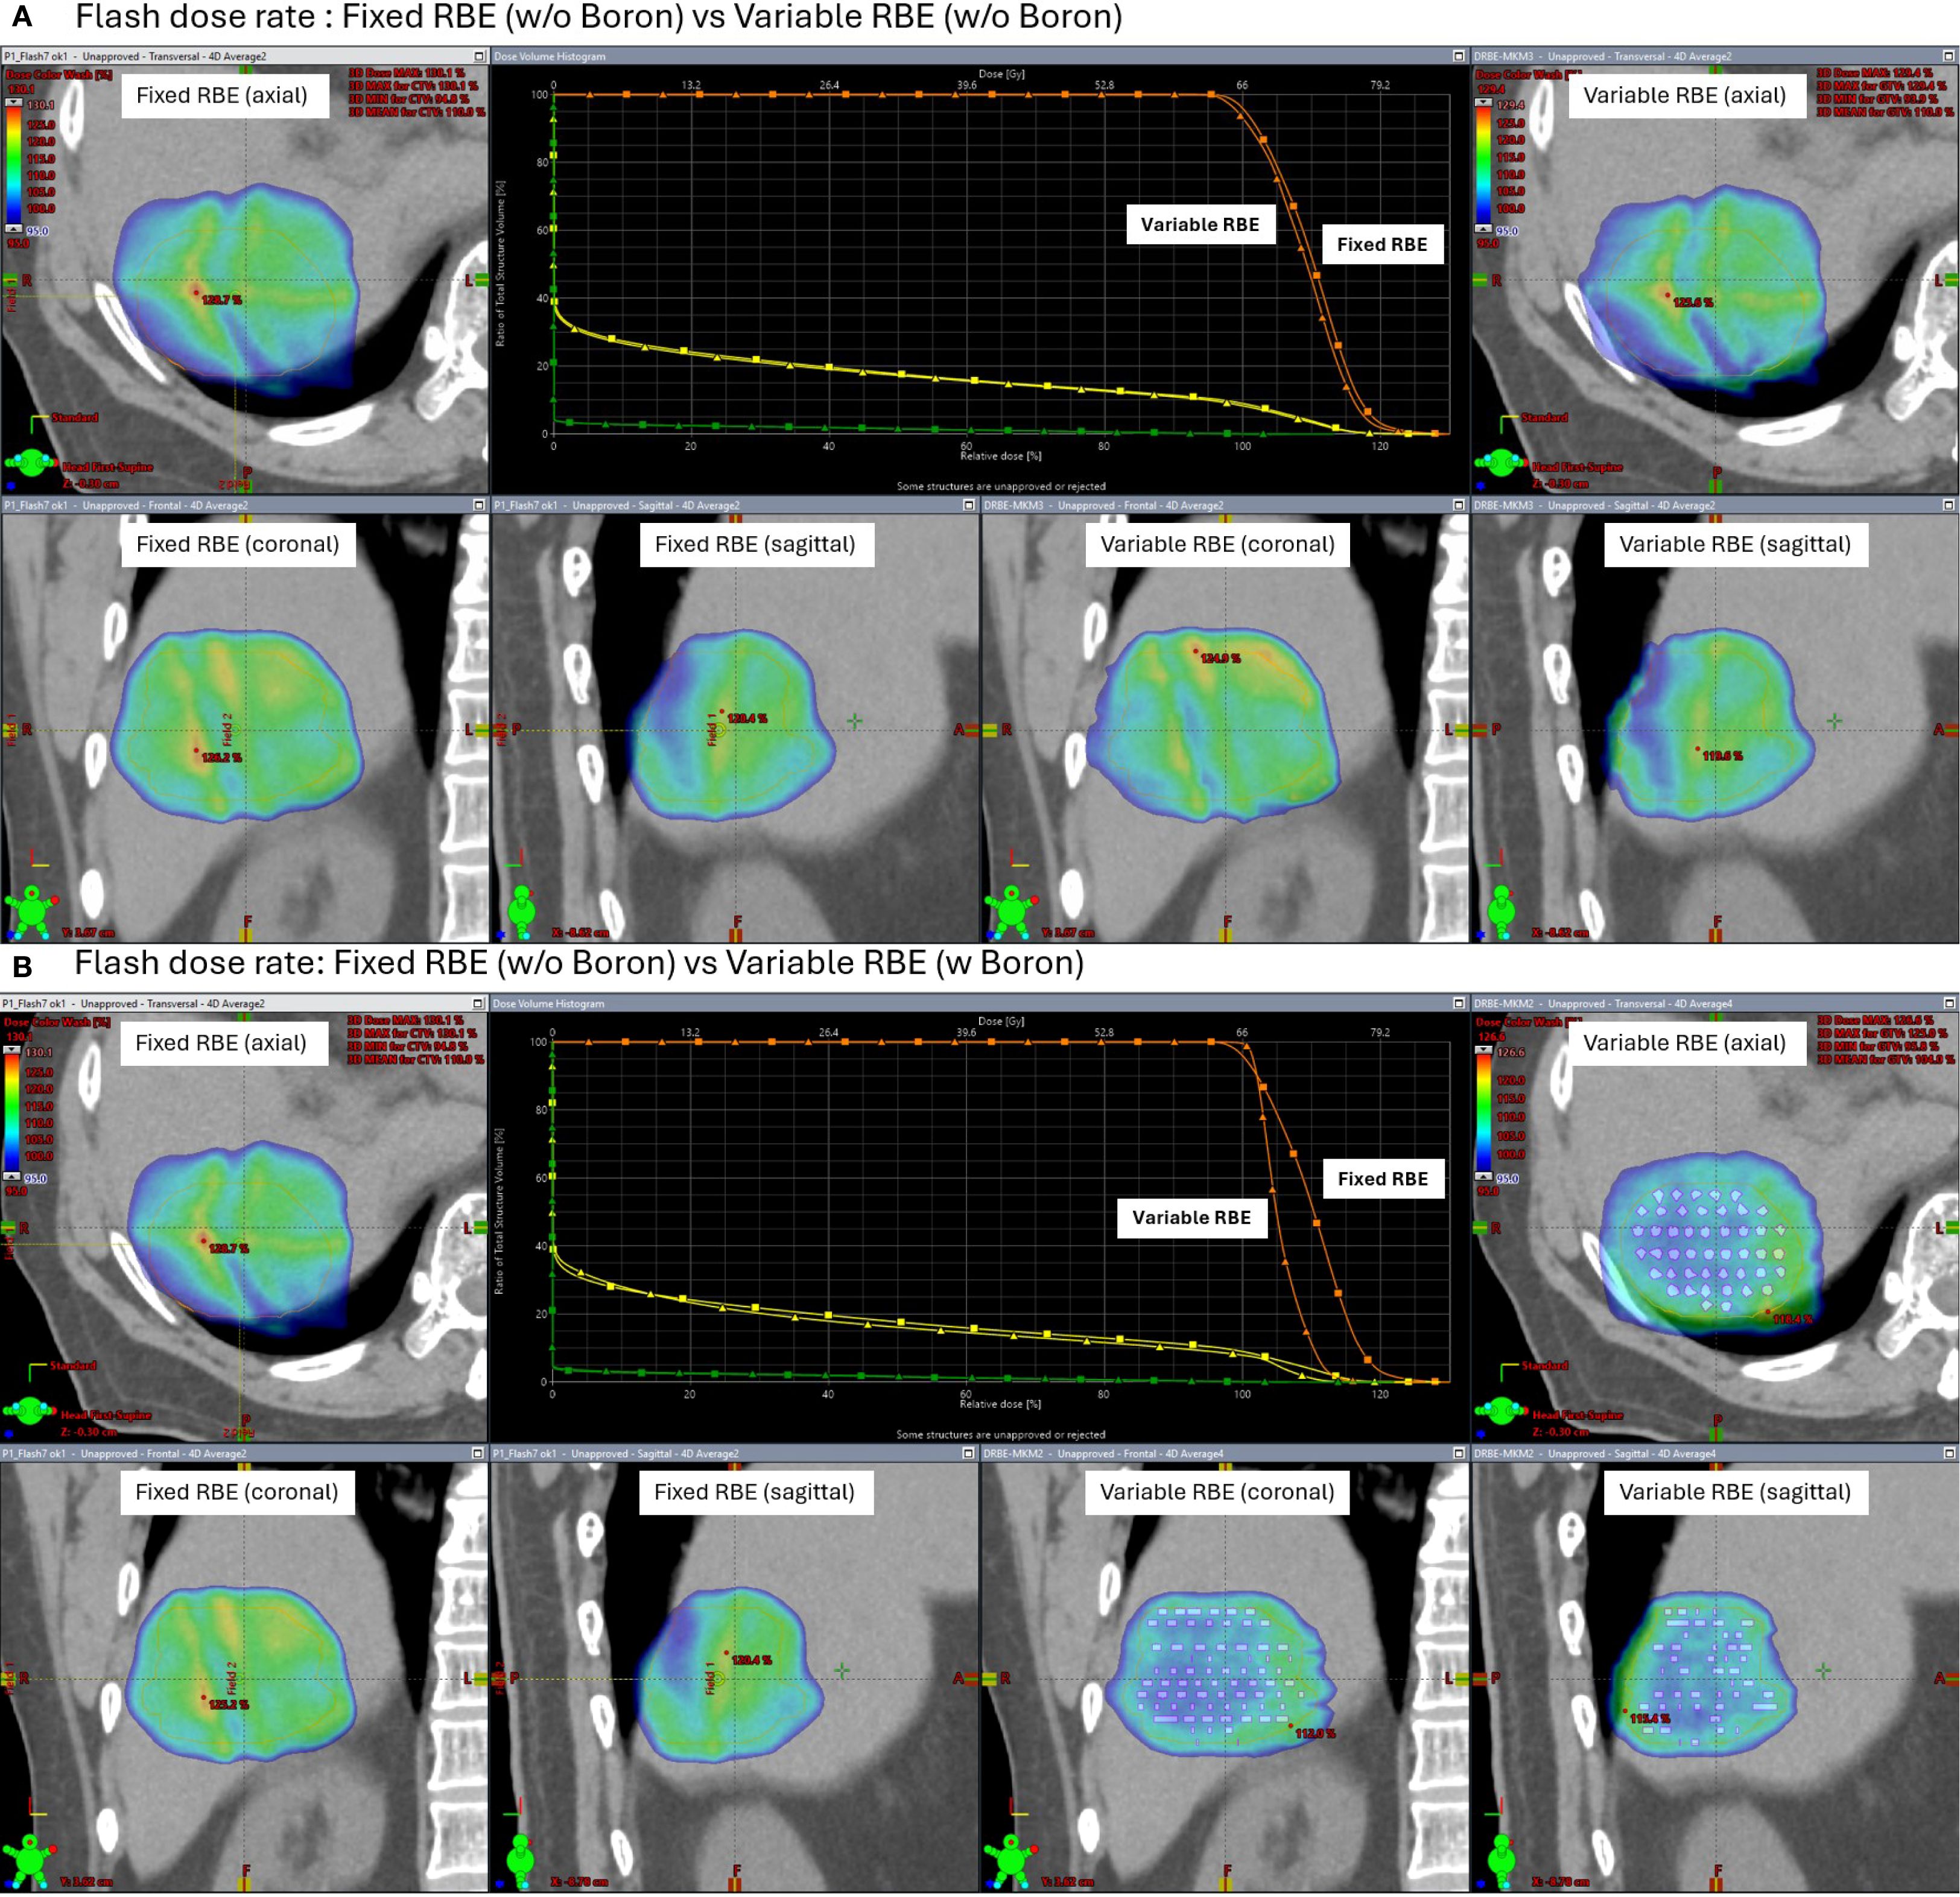

Under FLASH dose-rate conditions (Figure 8), the difference between fixed and variable RBE distributions was reduced even without the insert suggesting that FLASH delivery may inherently mitigate LET-driven dose variations. When the high-density region was added under FLASH, further improvement in dose homogeneity was observed, reinforcing the idea that both dose rate and local stopping power changes can influence biological dose shaping.

Figure 8

Panel A and B depict comparisons between fixed and variable relative biological effectiveness (RBE) at flash dose rates with and without Boron. Each panel includes CT images in axial, coronal, and sagittal views, highlighting dose distributions with color maps. A central graph shows dose-response curves comparing fixed and variable RBE metrics. Differences in dose distributions are visibly marked in the panels, emphasizing the impact of Boron.Figure 8. Simulated axial dose distributions and DVH under FLASH proton therapy (200 MU/spot). Comparisons are shown between fixed RBE and variable RBE models, both without (A) and with (B) a high-density boron insert in the clinical target volume (CTV). FLASH conditions reduce fixed-variable RBE differences, and the high-density boron insert region further improves biological dose uniformity.